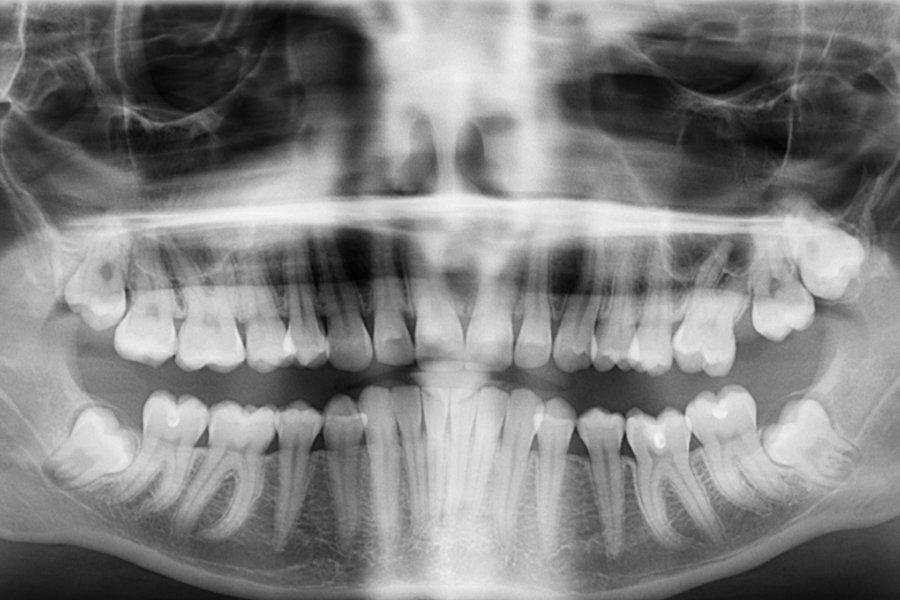

Для первичного приема в сети клиник необходимо принести панорамный снимок и снимок в 3D. Второй нужно делать непосредственно на этапах планирования операции, чтобы стоматологи понимали, как выгялдит челюсть.

Вживляемые импланты - это "объемная картинка". Поэтому стоматологам необходимо понимание того, как выглядит костная ткань во рту пациента на 360 градусов. Именно это позволяет увидеть объемный снимок КТ, т.е трехмерное изображение.